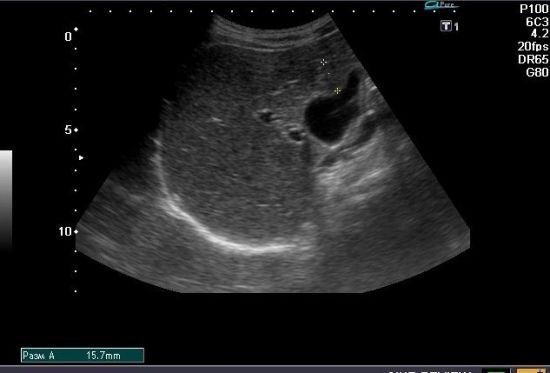

| Ультразвукове дослідження (УЗД) | Визначає зміни в структурі печінки, виявляє набряки або вузли |